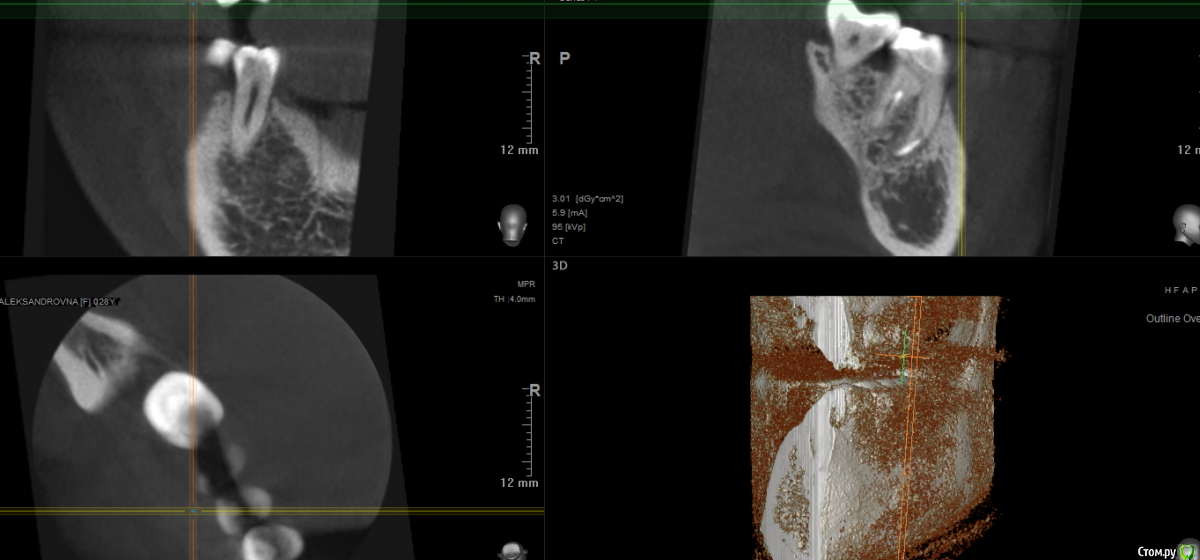

В общем, сходила я в другую клинику, сделали рентген, посмотрели, выписали антибиотики, дали месяц зубу, коронку на него нельзя, и по их словам даже если выживет, то около года протянет. На сегодняшний день, изменения не особо: в определенном смыкании боль осталась, бывает даже от прикосновения к зубу, не сильная, либо я за полгода лечения привыкла к ней. На днях сделала 3д снимок, хотелось бы узнать мнение профи: делать имплант, одноэтапный? надо наращивать кость? или всё же ещё раз перелечить зуб?

post-57643-0-20629800-1555936953_thumb.png